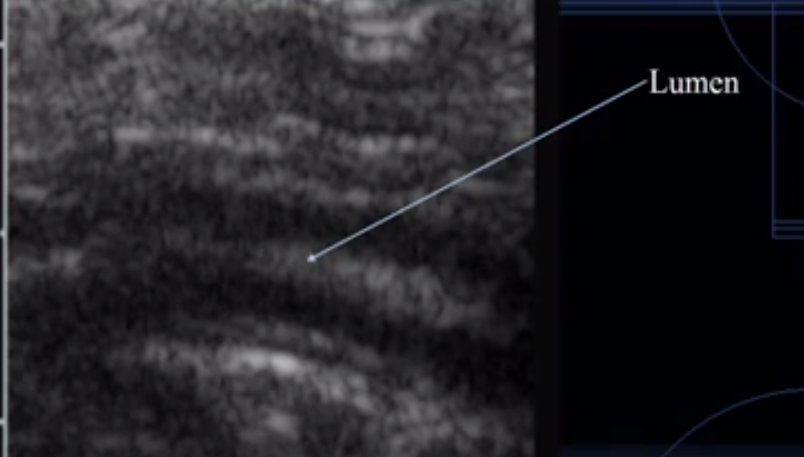

What does this image show?

Intestine

Which is the lumen?

Which is the mucosal layer?

Which is the submucosa layer?

Which is the muscularis layer?

Which is the serosal layer?